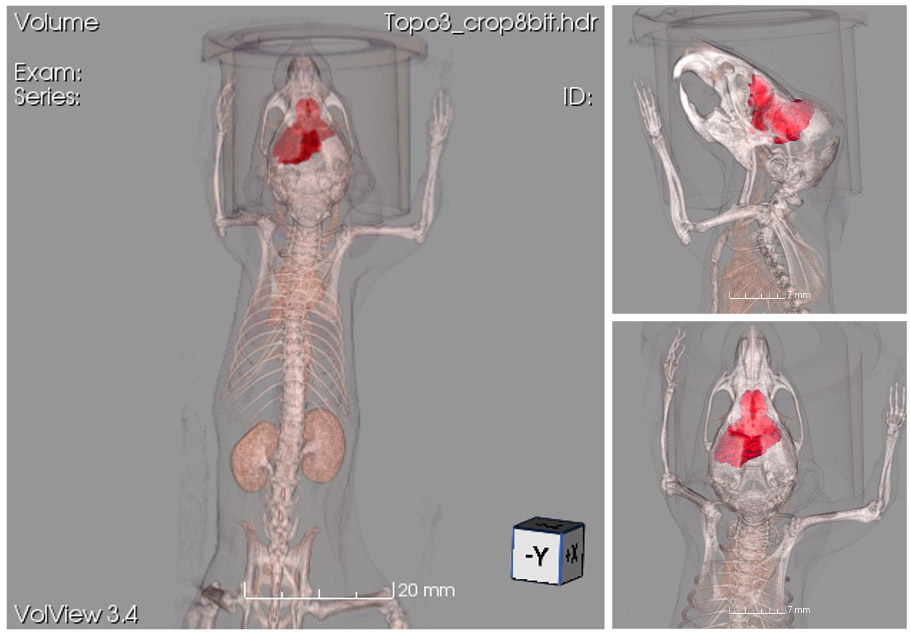

CASE 1: Mouse CT imaging with segmentation of adipose tissues

workimg

• Courtesy of: D.Panetta and P.A. Salvadori, IFC-CNR Pisa, Italy

Research objective: Non-enhanced micro-CT image of a mouse, showing an example of quantitative segmentation (RED = Brown Adipose Tissue - BAT; CYAN = abdominal visceral white adipose tissue - WAT; GREEN - Lungs).

Animal model: Mouse, 20-25g

Acquisition protocol: 3 min acquisition time, 1 bed position, 55 kVp, 1 mA

Processing and reconstruction protocol: 0.08 mm isotropic voxel size

Biomarker or contrast agent: No tracer applied